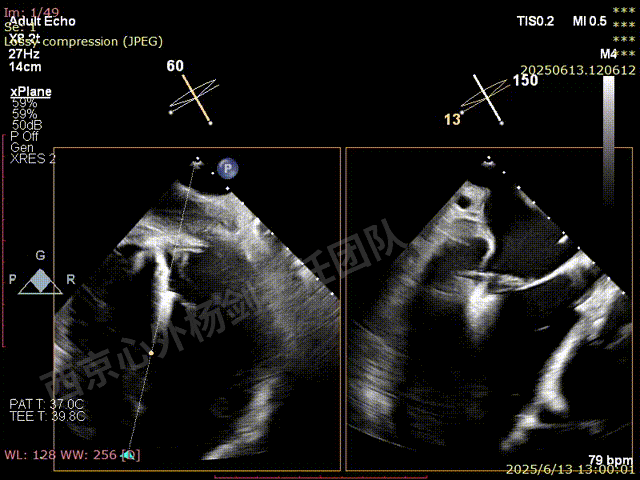

第二枚XT关闭后评估,trace

二尖瓣平均跨瓣压差1mmHg

释放后评估,反流降至1+,组织桥稳定

SGC撤回右房后,观察到有右向左的反流,血氧饱和度下降

行房间隔封堵

M-TEER术后三尖瓣反流减轻